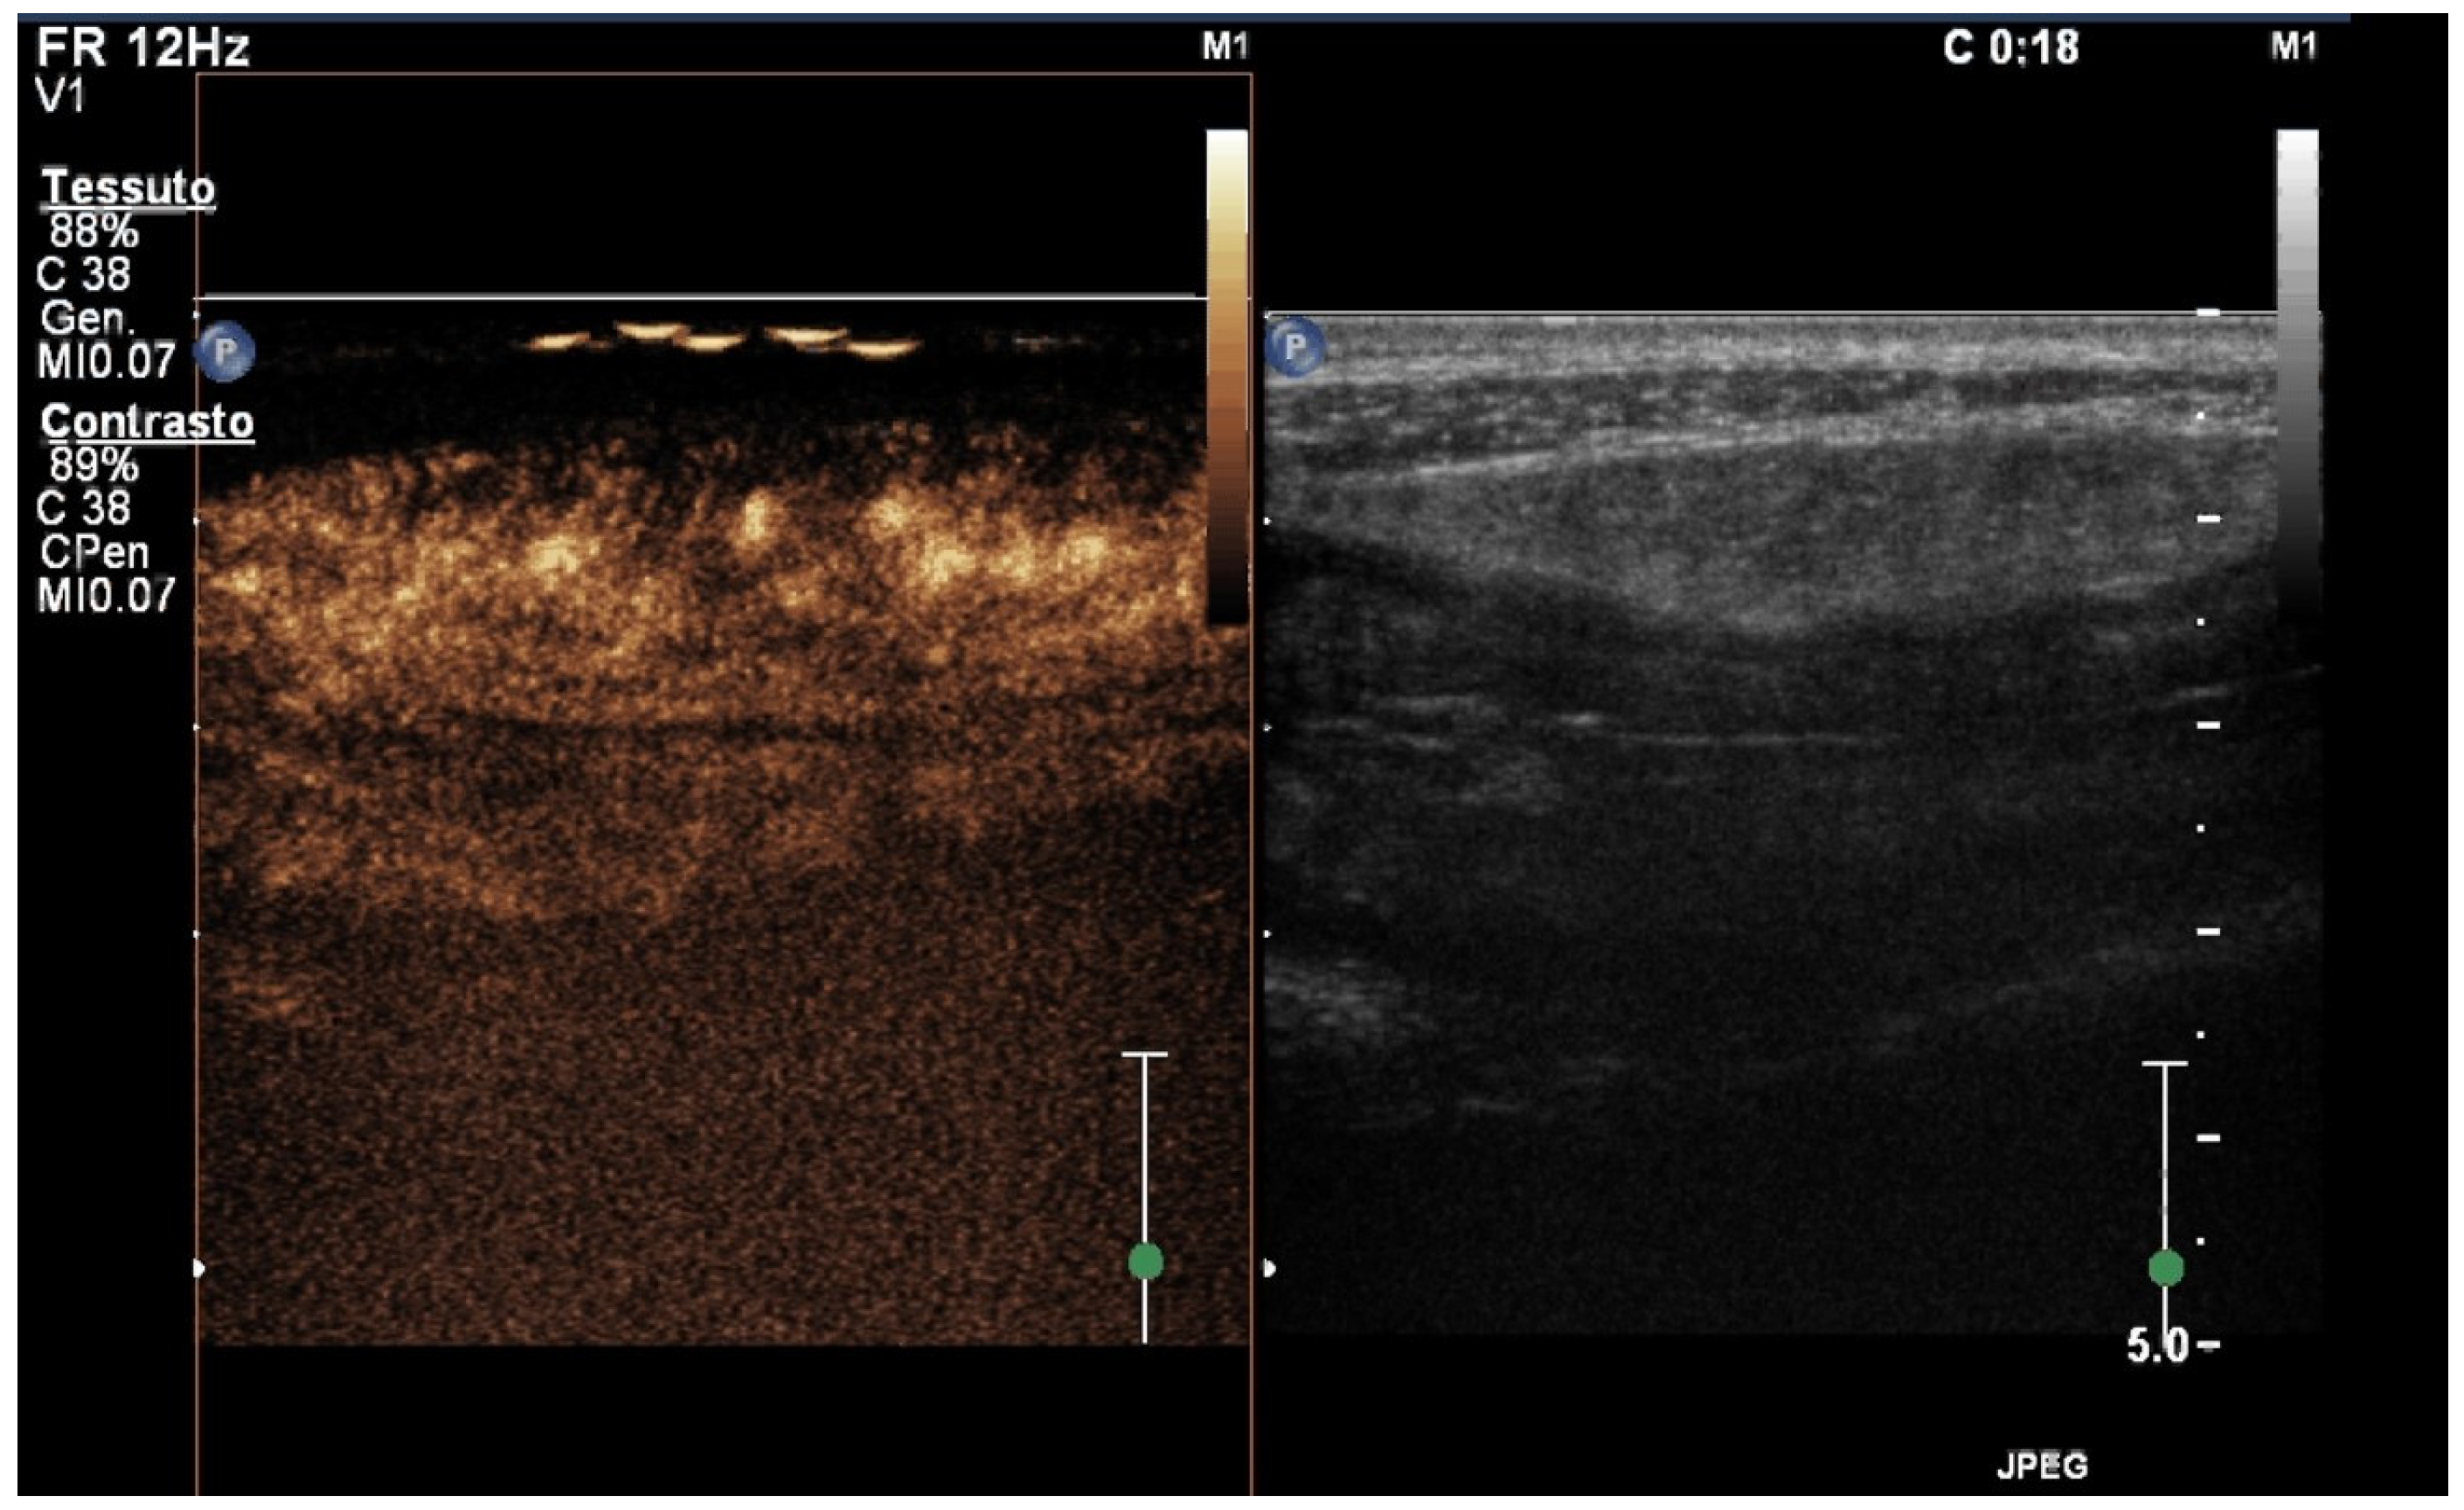

5. Contrast-Enhanced Ultrasound (CEUS)

- Medellin, A.; Merrill, C.; Wilson, S.R. Role of contrast-enhanced ultrasound in evaluation of the bowel. Abdom. Radiol. 2018, 43, 918–933. [Google Scholar] [CrossRef]

- Versluis, M.; Stride, E.; Lajoinie, G.; Dollet, B.; Segers, T. Ultrasound Contrast Agent Modeling: A Review. Ultrasound Med. Biol. 2020, 46, 2117–2144. [Google Scholar] [CrossRef] [PubMed]

- Paratore, M.; Garcovich, M.; Ainora, M.E.; Riccardi, L.; Gasbarrini, A.; Zocco, M.A. Dynamic contrast enhanced ultrasound in gastrointestinal diseases: A current trend or an indispensable tool? World J. Gastroenterol. 2023, 29, 4021–4035. [Google Scholar] [CrossRef] [PubMed]

- Migaleddu, V.; Scanu, A.M.; Quaia, E.; Rocca, P.C.; Dore, M.P.; Scanu, D.; Azzali, L.; Virgilio, G. Contrast-enhanced ultrasonographic evaluation of inflammatory activity in Crohn’s disease. Gastroenterology 2009, 137, 43–52. [Google Scholar] [CrossRef] [PubMed]

- Serafin, Z.; Białecki, M.; Białecka, A.; Sconfienza, L.M.; Kłopocka, M. Contrast-enhanced Ultrasound for Detection of Crohn’s Disease Activity: Systematic Review and Meta-analysis. J. Crohn’s Coli. 2016, 10, 354–362. [Google Scholar] [CrossRef]

- Ripollés, T.; Rausell, N.; Paredes, J.M.; Grau, E.; Martínez, M.J.; Vizuete, J. Effectiveness of contrast-enhanced ultrasound for characterisation of intestinal inflammation in Crohn’s disease: A comparison with surgical histopathology analysis. J. Crohn’s Coli. 2013, 7, 120–128. [Google Scholar] [CrossRef] [PubMed]

- Ripollés, T.; Paredes, J.M.; Martínez-Pérez, M.J.; Rimola, J.; Jauregui-Amezaga, A.; Bouzas, R.; Martin, G.; Moreno-Osset, E. Ultrasonographic Changes at 12 Weeks of Anti-TNF Drugs Predict 1-year Sonographic Response and Clinical Outcome in Crohn’s Disease: A Multicenter Study. Inflamm. Bowel Dis. 2016, 22, 2465–2473. [Google Scholar] [CrossRef]

- Laterza, L.; Ainora, M.E.; Garcovich, M.; Galasso, L.; Poscia, A.; Di Stasio, E.; Lupascu, A.; Riccardi, L.; Scaldaferri, F.; Armuzzi, A.; et al. Bowel contrast-enhanced ultrasound perfusion imaging in the evaluation of Crohn’s disease patients undergoing anti-TNFα therapy. Dig. Liver Dis. 2021, 53, 729–737. [Google Scholar] [CrossRef] [PubMed]